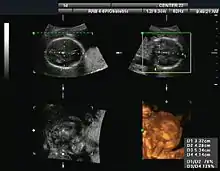

Obstetrical sonography was originally developed in the late 1950s and 1960s by Sir Ian Donald[19][20] and is commonly used during pregnancy to check the development and presentation of the fetus. It can be used to identify many conditions that could be potentially harmful to the mother and/or baby possibly remaining undiagnosed or with delayed diagnosis in the absence of sonography. It is currently believed that the risk of delayed diagnosis is greater than the small risk, if any, associated with undergoing an ultrasound scan. However, its use for non-medical purposes such as fetal "keepsake" videos and photos is discouraged.[21]

Obstetric ultrasound is primarily used to:

- Date the pregnancy (gestational age)

- Confirm fetal viability

- Determine location of fetus, intrauterine vs ectopic

- Check the location of the placenta in relation to the cervix

- Check for the number of fetuses (multiple pregnancy)

- Check for major physical abnormalities.

- Assess fetal growth (for evidence of intrauterine growth restriction (IUGR))

- Check for fetal movement and heartbeat.

- Determine the sex of the baby